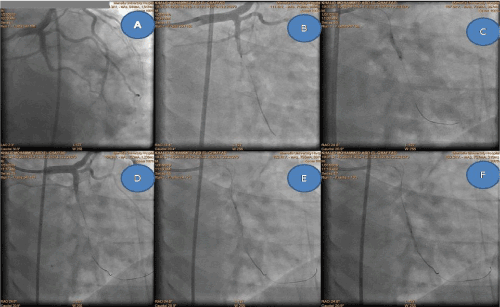

Figure 1.  Total occlusion of mid part LCX A, then stepped procedure of deforming the plaque B, C, D, E, F by 2 wires with different balloons sizes and POT fashioned technique